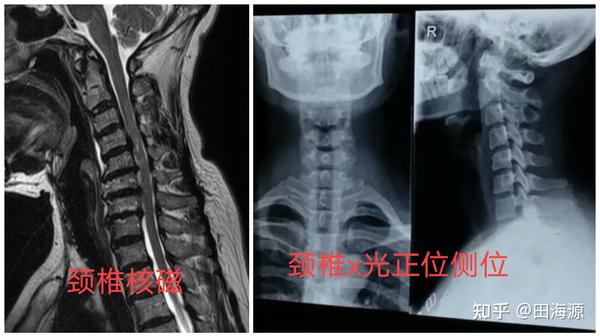

颈椎核磁共振和 颈椎x光片正位侧位,除此之外,啥也不需要.